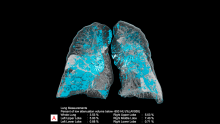

January 31, 2020 — One of the first imaging studies on the coronavirus (2019-nCoV) was published online today as radiologists scramble to find out how the virus presents in medical imaging. In just 30 days after the virus first appeared in China, it has spread to more than 8,200 confirmed cases and more than 170 deaths. Cases are now being reported in several countries, including the United States and Canada.